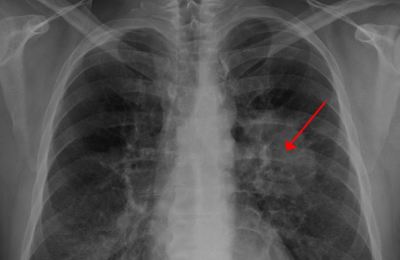

이러한 폐암의 원인으로 인해 폐암으로 진단되기 전에 폐암 초기증상을 조기에 발견하면 다른 장기로의 전이나 진행성 폐암으로의 진행을 어느 정도 지연시키거나 적절하게 치료할 수 있지만 일반적으로 폐암의 초기 단계는 특별한 징후나 증상이 없으므로 조기에 발견하는 경우는 극히 드뭅니다.

폐암 초기에는 기침이 잦거나 가래가 끓는 등 감기와 같은 증상이 나타날 수 있다. 따라서 폐암은 초기에 암인지 판단하기 어렵다. 또한 객담이나 적혈구를 동시에 토하는 것도 폐암을 진단하는 가장 중요한 증상 중 하나이다. 붉은 피가 섞인 가래 증상이 있으면 병원에 가서 검사를 받아야 한다.

또는 가래, 기침, 목소리가 쉬지 못하는 등 가벼운 감기라고 생각하여 폐암이 진행된 후에 종양이 발견되는 경우가 많습니다. 폐렴은 또한 기관지의 감염성 종양을 동반할 수 있습니다. 또한, 그럼에도 불구하고 폐렴만을 중심으로 치료를 하다 보면 상세한 검사 결과로 인해 종양을 식별하지 못하거나 폐암으로 발전할 수 있습니다.